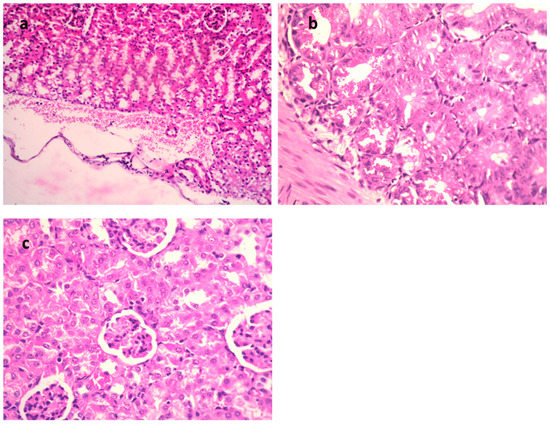

| Necrobiotic changes in tubular epithelium | − | +++ | + | + |

| Interstitial inflammatory cell infiltration | − | + | − | + |

| Interstitial hemorrhage | − | + | − | − |

| Subcapsular hemorrhage | − | +++ | − | − |

| Renal cast | − | − | + | − |